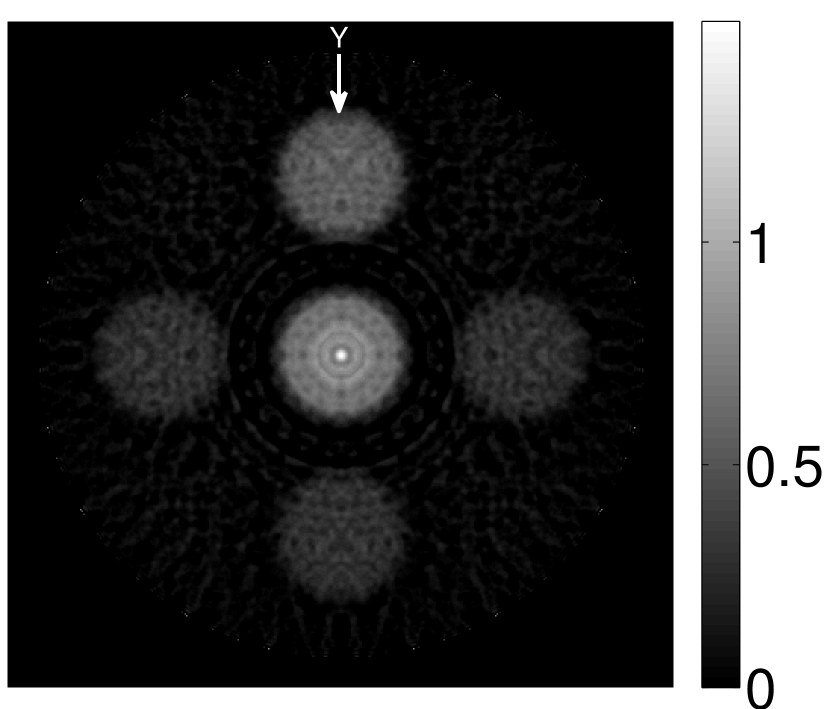

V-A3 Effect of data incompleteness

Incomplete, or sparsely sampled, data sets are sometimes acquired in practice. To study the effect of data incompleteness on the VP algorithm, we reconstructed images from data corresponding to half of the equally spaced transducers (). Because the data were noiseless, no explicit regularization was employed () in the conventional reconstruction algorithm. However, the explicit regularization was still employed in the VP algorithm because of the ill-posed nature of the joint reconstruction problem. The results are shown in Figure 5. As expected, use of the incomplete data set resulted in less accurate reconstructed images for both the conventional iterative reconstruction method and the VP algorithm. However, this effect was more pronounced for the VP algorithm. Note that for the VP algorithm, larger values of the regularization parameters were applied when the incomplete data set was employed than when the complete data set was employed (Figure 5(h) and 5(g)).